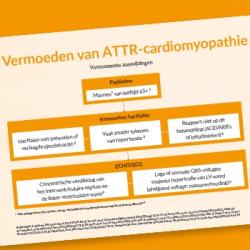

Vermoeden van ATTR-cardiomyopathie

Handig symptomen schema bij vermoeden van ATTR-cardiomyopathie.